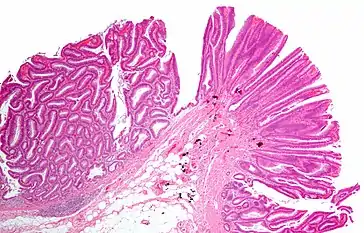

Adénome villeux

Les adénome villeux, plus rares, forment des masses sessiles ou polypoïdes, molles, recouvertes de mucus, et constituées de fines digitations. Elles sont constitués d'axes conjonctifs recouverts d'une couche de cellules épithéliales cylindriques et mucosecrétantes, comportant ou non une mucosécrétion comme l'épithélium colique superficiel dont elles dérivent.

Comme les adénomes tubuleux, les tumeurs villeuses peuvent présenter des aspects dédifférenciés. Les récidives après exérèse sont très fréquentes.

Adénome tubulo-villeux

Les adénome tubulo-villeux sont mixtes, à la fois tubuleux et villeux.